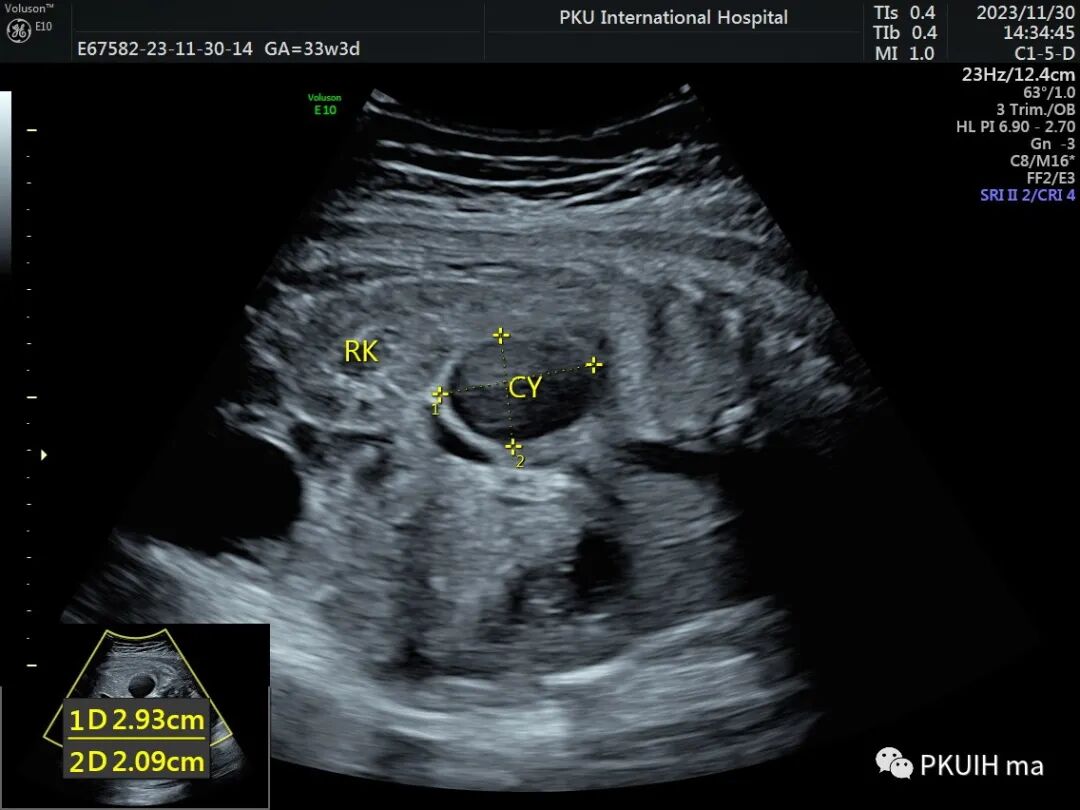

孕妇在之前超声检查中均未见异常,在28周常规超声筛查中发现右侧肾上腺区见一囊肿回声,大小约1.3x1.0cm。随访观察中发现囊肿逐渐增大,胎儿其他各项指标未见明显异常。目前仍在定期随访中